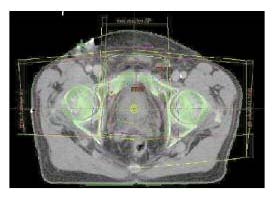

Technika a plánování radioterapie

Poloha pacienta: Pacient se ozařuje v supinační poloze na zádech s

podložením kolenních kloubů (vyrovnání lumbální lordózy).

Plánování: RT simulátor, CT plánovací vyšetření (vhodný p.o. a i.v.

kontrast), 3D plánovací systém, event. i MR plánování nebo

PET/CT.

Technika: Kombinace tří konvergentních polí (maximální šetření

rekta), event. kombinace čtyř polí, BOX technika. Tvar polije

individuálně upraven vykrývacími bloky nebo vícelamelovým

kolimátorem (MLC).

Pozn.: Při plánování radioterapie celé pánve (PTV 1) jsou pacienti

s plným močovým měchýřem. Při plánování záření jen na oblast

močového měchýře (PTV 2,3) jsou s prázdným močovým měchýřem - tzn.

provedení min. dvou CT plánovacích vyšetření.